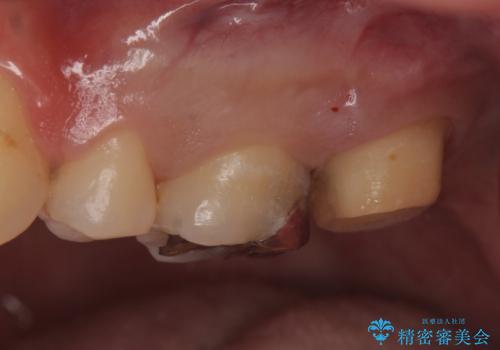

①ジルコニアクラウンによる治療

表面のザラザラは消えるが健全な歯質を多く削ることになる。

以上の提案より患者様に考えてもらい、①をご希望されたのでジルコニアクラウンによる治療を行った。

- フルジルコニアクラウン・仮歯 8.8万円費用は治療当時の料金となります